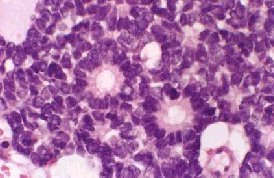

Flexner Wintersteiner rosettes: clusters of cuboidal or short columnar cells arranged around a central lumen. The nuclei are

displaced away from lumen.

Homer Wright rosettes: radial arrangements of cells around a central tangle of fibrils. (pseudorosette).

Fleurette (arrowed): photoreceptor differentiation.